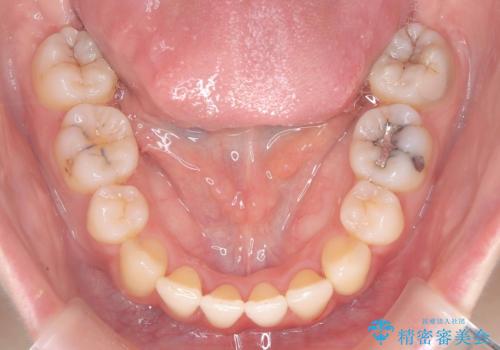

- 矯正装置

- ワイヤー(審美装置)

抜歯矯正により歯列のデコボコ(叢生)が改善し、前歯の突出も解消されたことで口元が下がり、すっきりとした印象となりました。

患者様にも大変ご満足いただけました。